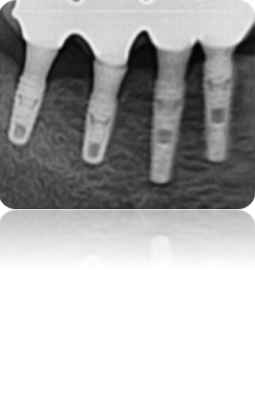

변연골 소실 최소화

- 평균 관촬 기간: 13.4 months

- 평균 변연골 소실량 : 0.027± 0.0138 mm (총 144개 임플란트)

INNO Submerged

INNO 임플란트 144개 평균 변연골 소실

0.027 ± 0.0138 mm

Other Implant

1년 평균 변연골 소실

0.21 ~ 0.99 mm

Atieh et al.(2010)의 검토에 따르면 1년 추적 관찰

기간 동안 플랫폼 전환 임플란트 주변의 평균

변연골 소실은 0.021~0.99mm였습니다.